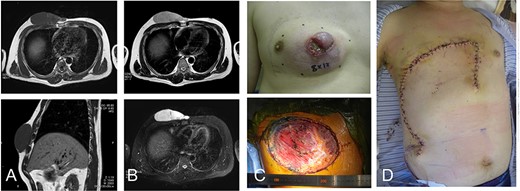

A 42-year-old man presented with a history of a mass on his right chest wall that gradually increased in size over 2–3 years. On physical examination, a protuberant hard, immobile elastic mass that appeared attached to the fascia was palpable on the anterior chest wall. Magnetic resonance imaging (MRI) revealed an 8 × 12-cm subcutaneous tumor. The tumor showed homogenous low-signal intensity on the T1-weighted image and high-signal intensity on the T2-weighted image (Fig. 1A and B). The tumor was attached to the fascia of the pectoralis major muscle.

42-year-old male with dermatofibrosarcoma protuberans in the chest wall. Magnetic resonance imaging shows the subcutaneous tumor with low-signal intensity on the T1-weighted image (A) and slightly high-signal intensity on the T2-weighted image (B-upper) and high-signal intensity on a T2-weighted fat-suppressed image (B-lower); photograph of ulcerated subcutaneous lesion with subcutaneous extension; after resection of the tumor with the surrounding tissue (C), the defect was reconstructed with a thoracoabdominal flap (D).

Histological examination of a needle biopsy specimen revealed a dermatofibrosarcoma protuberans. The tumor was resected along with the surrounding skin, subcutaneous tissue, and the underlying pectoralis major muscle, leaving a defect of 16 cm in the maximum diameter (Fig. 1C). The defect was reconstructed with a medially-based thoracoabdominal flap (Fig. 1D).